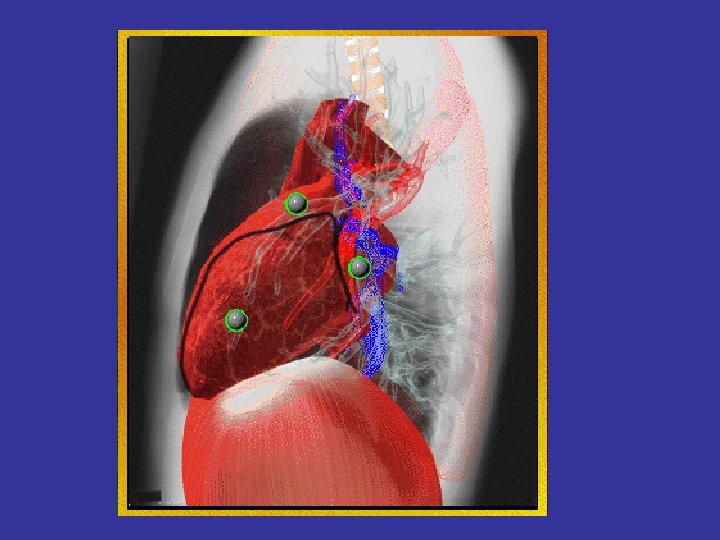

Left atrial enlargement in mitral stenosis

Left atrial enlargement